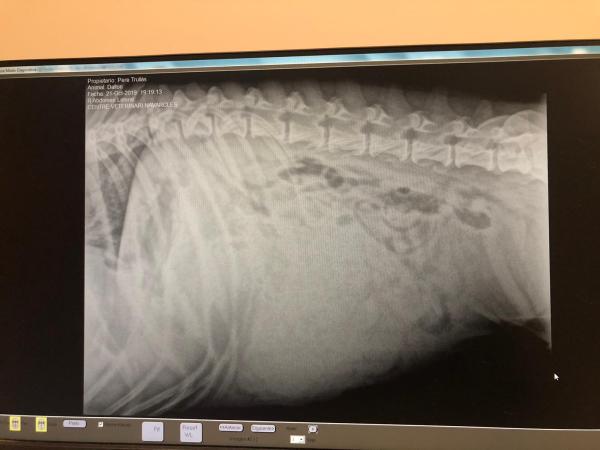

Es cierto que con este método se tiende a subestimar camadas pequeñas e infravalorar las camadas grandes. No es 100% exacto. Por este motivo, muchos expertos recomiendan hacía el final de la gestación someter a la perra a una radiología, cuando los cachorros son mas fuertes para comprobar exactamente el estado de los fetos y la cantidad. Te recordamos que este tipo de prueba sí es algo perjudicial para la salud de tu mascota, aún así, el veterinario te aconsejará si debes hacerlo o no para la seguridad del parto.

hola!! me podriais ayudar aver si podeis ver que tiene mi perro? le an echo una radiografia..i me a dicho el veterinario que es mejor que le aga una ecografia..porque n sabe ver que tiene..pero que piede ser un tumor..es un american estanffor de 10 años..